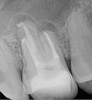

Fig 4. and Fig 5. Before and after radiographs of bioceramic sealer hydraulically moved with the gutta-percha point. Note that the cold hydraulic technique results in lateral canal “puffs” similar to the warm vertical technique. Courtesy of Dr. Gilberto Debelian.

Pre-mixed BC Sealer is the only pure medical-grade bioceramic product available as a sealer for endodontic obturation. It has the same basic chemical composition as the other pre-mixed bioceramic products, but it is less viscous, which makes its consistency ideal for sealing root canals. It is used with a gutta-percha point, which is impregnated on the surface with a nano particle layer of bioceramic. The gutta-percha is used primarily as the delivery device (plugger) (Figure 1 through Figure 3) to allow hydraulic movement of the sealer into the irregularities of the root canal and accessory canals (Figure 4 and Figure 5).

This sealer solves most, if not all, of the previous problems of traditional sealers. Therefore, a thicker layer of sealer can be used because it is dimensionally stable and does not wash out. The core is used only as a hydraulic pump to move the sealer into place and allow for post space preparation or a pathway for retreatment. In addition and most importantly, the root canal preparation can be conservative and better adapted to restorative needs, since a traditional gutta-percha point (and not a metal plugger) is used to move the filling material. An additional benefit of the system is that there are now gutta-percha points that are impregnated with nano particles of bioceramics, so the sealer bonds not only to the root surface but also to the outer surface of the gutta-percha, eliminating the gap between the two (Figure 19 through Figure 21).